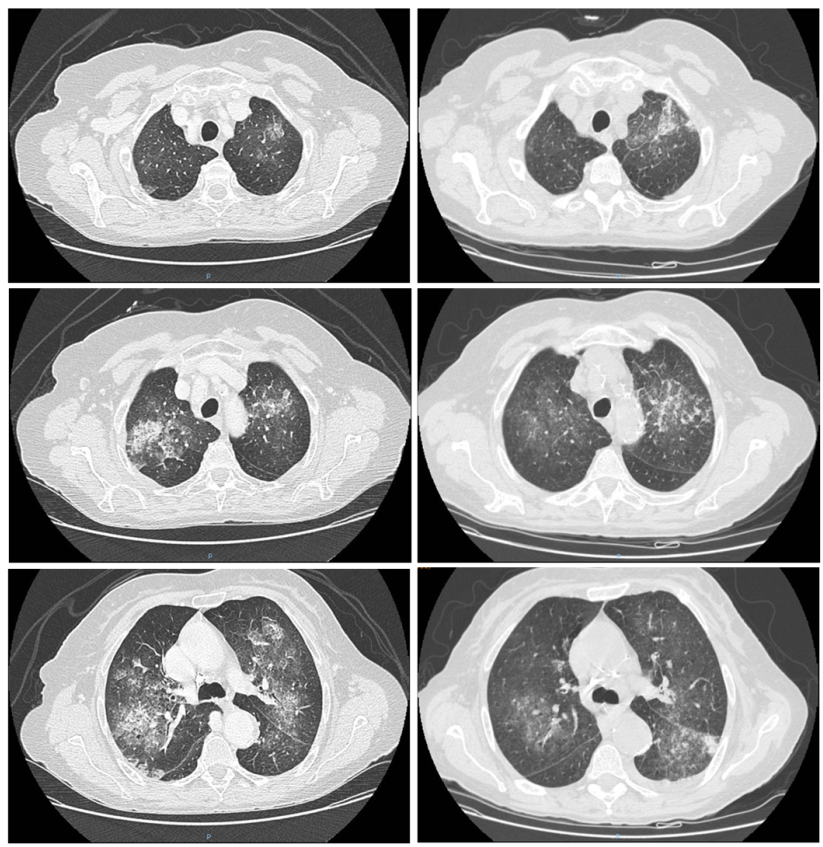

During hospitalisation, haemoglobin values improved, but significant respiratory failure persisted. In addition, hypereosinophilia persisted, reaching up to 5,000 cells/µl (33% of WBCs). Given this data and the presence of a recent further episode of pulmonary inflammation in the patient's medical history, a follow-up chest CT scan was performed.

As evident from the images, the CT scan confirmed the presence of multiple ground glass opacities in the lungs, with some lesions improving and others worsening, compared to the previous CT scan.

High-resolution chest CT scan. Images on the left refer to the CT scan performed one month before; images on the right refer to the CT scan performed during current hospitalisation. The comparison shows substantial changes in the previously described opacities, some of which have improved (right lung) and some of which have worsened radiologically (apex and upper segment of the left lung).